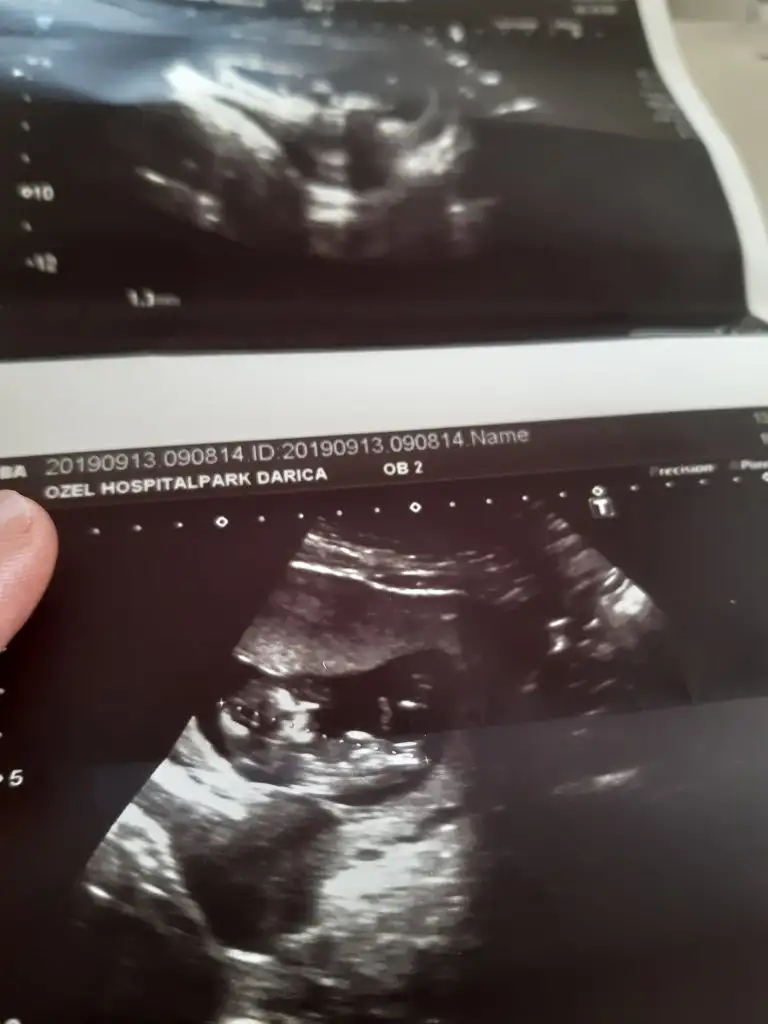

Bence de kız Canım direk usg ye baktım okumadan kız dedim doktor da aynısını demiş Allah bana da nasip ett inşallah böyle usgMerhabalar,bebeğim 12+5,doktorumuz kız dedi, mümkünse bende tahmin alabilir miyim

Erkek gibi geldi banaMerhabalar,bebeğim 12+5,doktorumuz kız dedi, mümkünse bende tahmin alabilir miyim